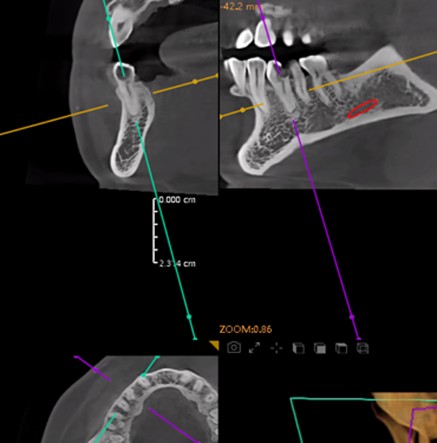

Postoperative CT scans and intraoral photographs were obtained.

Immediate implant placement (first-stage surgery) was performed right after tooth extraction.

After full communication with the patient, the residual root was extracted, and immediate implant placement was performed in the same surgical session. One bottle of bone graft material and one piece of collagen membrane were applied during the procedure. A 6-month healing period was scheduled. After achieving favorable osseointegration, the second-stage implant surgery was carried out, followed by impression taking, crown fabrication, and definitive crown placement.